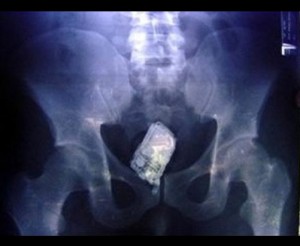

სამშენებლო ქაფი

12 (1)